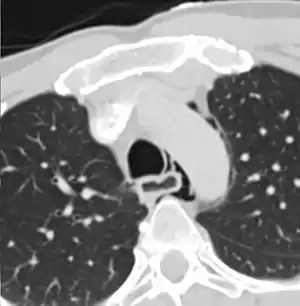

Axial CT image through the upper chest showing extraluminal air (pneumediastinum) surrounding the trachea and esophagus

The diagnosis of Boerhaave's syndrome is suggested on the plain chest radiography and confirmed by chest CT scan. The initial plain chest radiograph is almost always abnormal in patients with Boerhaave's syndrome and usually reveals mediastinal or free peritoneal air as the initial radiologic manifestation. With cervical esophageal perforations, plain films of the neck show air in the soft tissues of the prevertebral space.

Hours to days later, pleural effusion(s) with or without pneumothorax, widened mediastinum, and subcutaneous emphysema is typically seen. CT scan may show esophageal wall edema and thickening, extraesophageal air, periesophageal fluid with or without gas bubbles, mediastinal widening, and air and fluid in the pleural spaces, retroperitoneum or lesser sac.